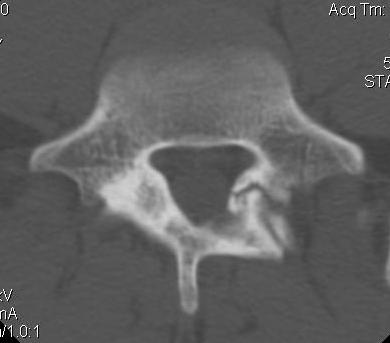

CT scan

Technique

- reverse gantry

Indication

- perform instead of obliques

- oblique x-rays have high radiation dose with little extra information compared with CT